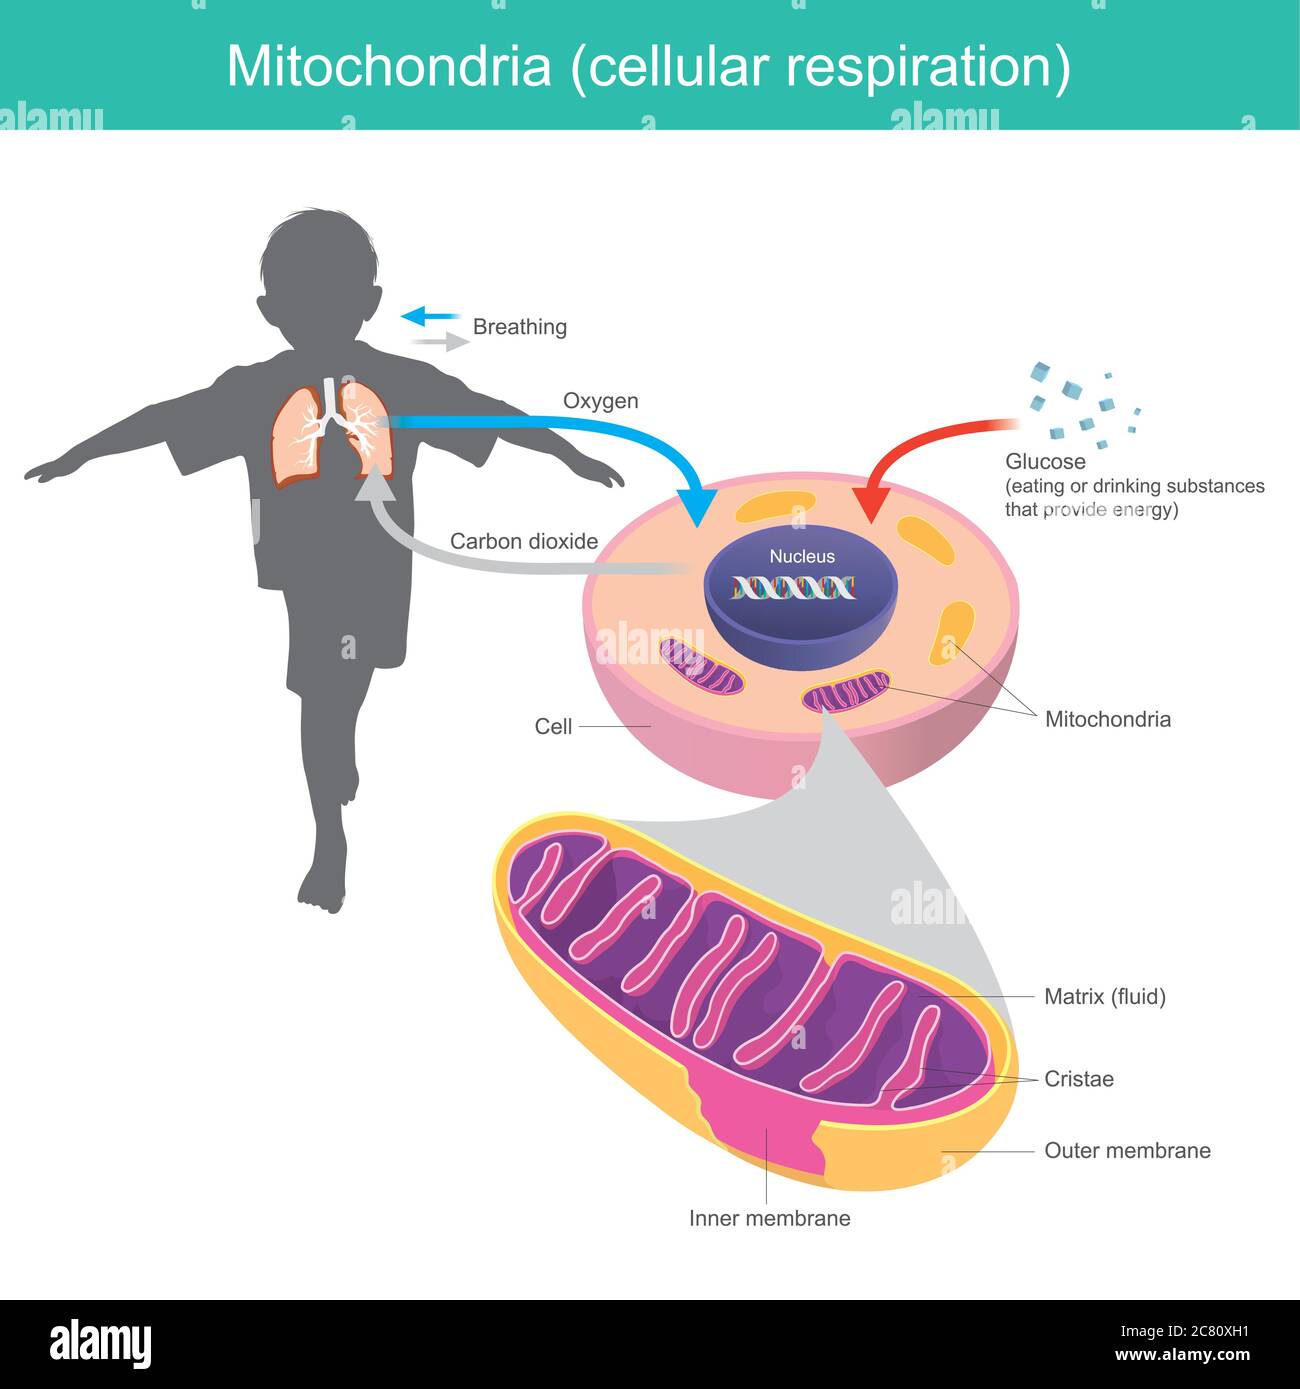

Mitocondri. Illustrazione spiegare che il corpo umano ha ricevuto glucosio e ossigeno come mangiare o bere dopo che il sistema cellulare cambia glucosio Illustrazione Vettorialehttps://www.alamy.it/image-license-details/?v=1https://www.alamy.it/mitocondri-illustrazione-spiegare-che-il-corpo-umano-ha-ricevuto-glucosio-e-ossigeno-come-mangiare-o-bere-dopo-che-il-sistema-cellulare-cambia-glucosio-image366355837.html

Mitocondri. Illustrazione spiegare che il corpo umano ha ricevuto glucosio e ossigeno come mangiare o bere dopo che il sistema cellulare cambia glucosio Illustrazione Vettorialehttps://www.alamy.it/image-license-details/?v=1https://www.alamy.it/mitocondri-illustrazione-spiegare-che-il-corpo-umano-ha-ricevuto-glucosio-e-ossigeno-come-mangiare-o-bere-dopo-che-il-sistema-cellulare-cambia-glucosio-image366355837.htmlRF2C80XH1–Mitocondri. Illustrazione spiegare che il corpo umano ha ricevuto glucosio e ossigeno come mangiare o bere dopo che il sistema cellulare cambia glucosio